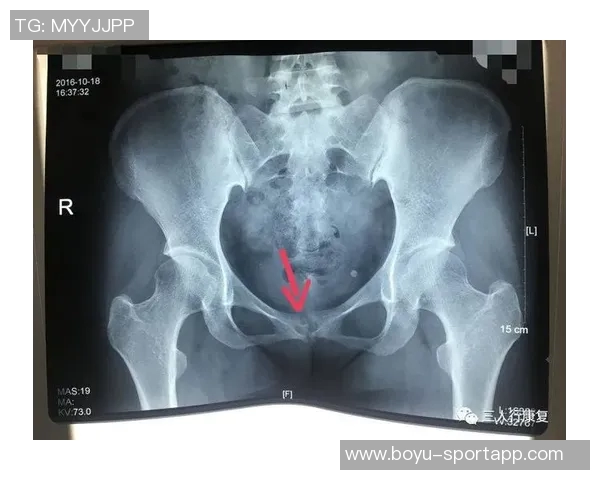

尼科·威廉姆斯是一名备受瞩目的年轻球员,他在比赛中表现出色,为球队贡献了许多关键进球。然而,在一次重要比赛中,他不幸遭遇了耻骨炎。这种疾病给他的训练和比赛造成了严重影响,让他不得不面对漫长而艰难的恢复过程。

初期,尼科并没有意识到自己的伤势有多严重。他依旧坚持参加训练,但随着时间推移,他逐渐感受到身体的不适。经过专业医生的检查后,他被确诊为耻骨炎,这让他深感沮丧,因为这意味着他需要停下脚步,进行长时间的康复治疗。